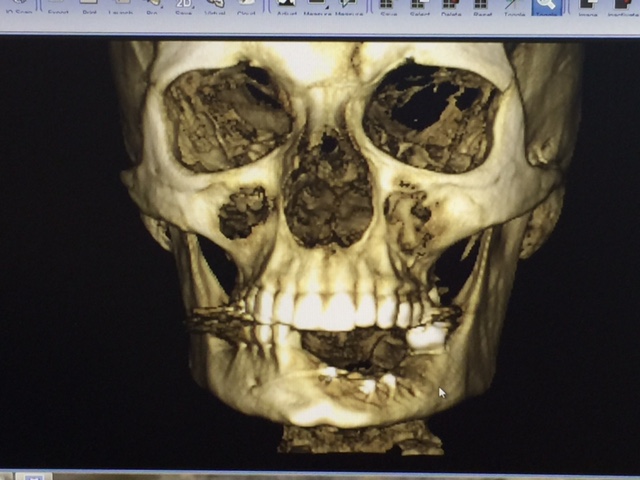

As most of you know, over the last year or so Kim has been battling medical issues after finding a Giant Cell Granuloma tumor in her bottom left jaw. Giant Cell Granuloma tumors are bone eating and although the original tumor was benign, the only way to ensure that it would stop growing or continuing to eat the bones in her jaw was to remove it. Of course, with tumor removal in the jaw came the loss of teeth and bones. After the first surgery in December of 2014, Kim faced the challenges of recovery plus an additional bone graph surgery in July of 2015 where part of her hip bone was surgically removed and placed in her jaw. After facing yet another round of recovery, this time in both her hip and her jaw, in December of 2015 the doctor's found a new tumor on the right side of her jaw that seems to be of the same type as the previous.

Following the biopsy, and if the doctor's anticipations of it being a second Giant Cell Granuloma tumor are true, that tumor, along with the teeth and part of the jaw it effects will need to be removed. At that point, Kim will have (hopefully) two remaining teeth in her bottom jaw.

In anticipation of the second tumor, Kim is still needing to address the reconstruction of the removal of the original tumor. At this stage, one-year post surgery, the plan is to begin the preparation for porcelain implants, or a new set of teeth. In order to do this, Kim will face a third surgery in which five metal posts will be implanted into the graphed bone in her jaw. This surgery cost is roughly $9,795. However, the quote only includes 30 minutes of general anesthesia, and the doctors anticipate surgery could take up to an hour and a half.

Once these two surgeries regarding the metal posts have occurred and recovery is successful, Kim will finally be given a new set of teeth on the left side. (Remember, this is without any knowledge of that second tumor of the right or the cost that will come with it). Although this seems far off in time at this point, the initial cost covers all surgeries and stages of the process regarding the porcelain implants. The current quote for the teeth and jaw replacement is $19,542.